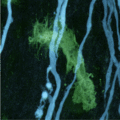

Sitemap > Media > News > Early Damage in multiple sclerosis can be reversed > In multiple sclerosis, immune cells (green) attack nerve-cell projections or axons (blue). Light microscopy picture of the spinal cord of a mouse.

In multiple sclerosis, immune cells (green) attack nerve-cell projections or axons (blue). Light microscopy picture of the spinal cord of a mouse.

Copyright: Thomas Misgeld and Martin Kerschensteiner / TUM and LMU